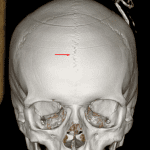

Age: 16

Sex: Male

Indication: Trauma